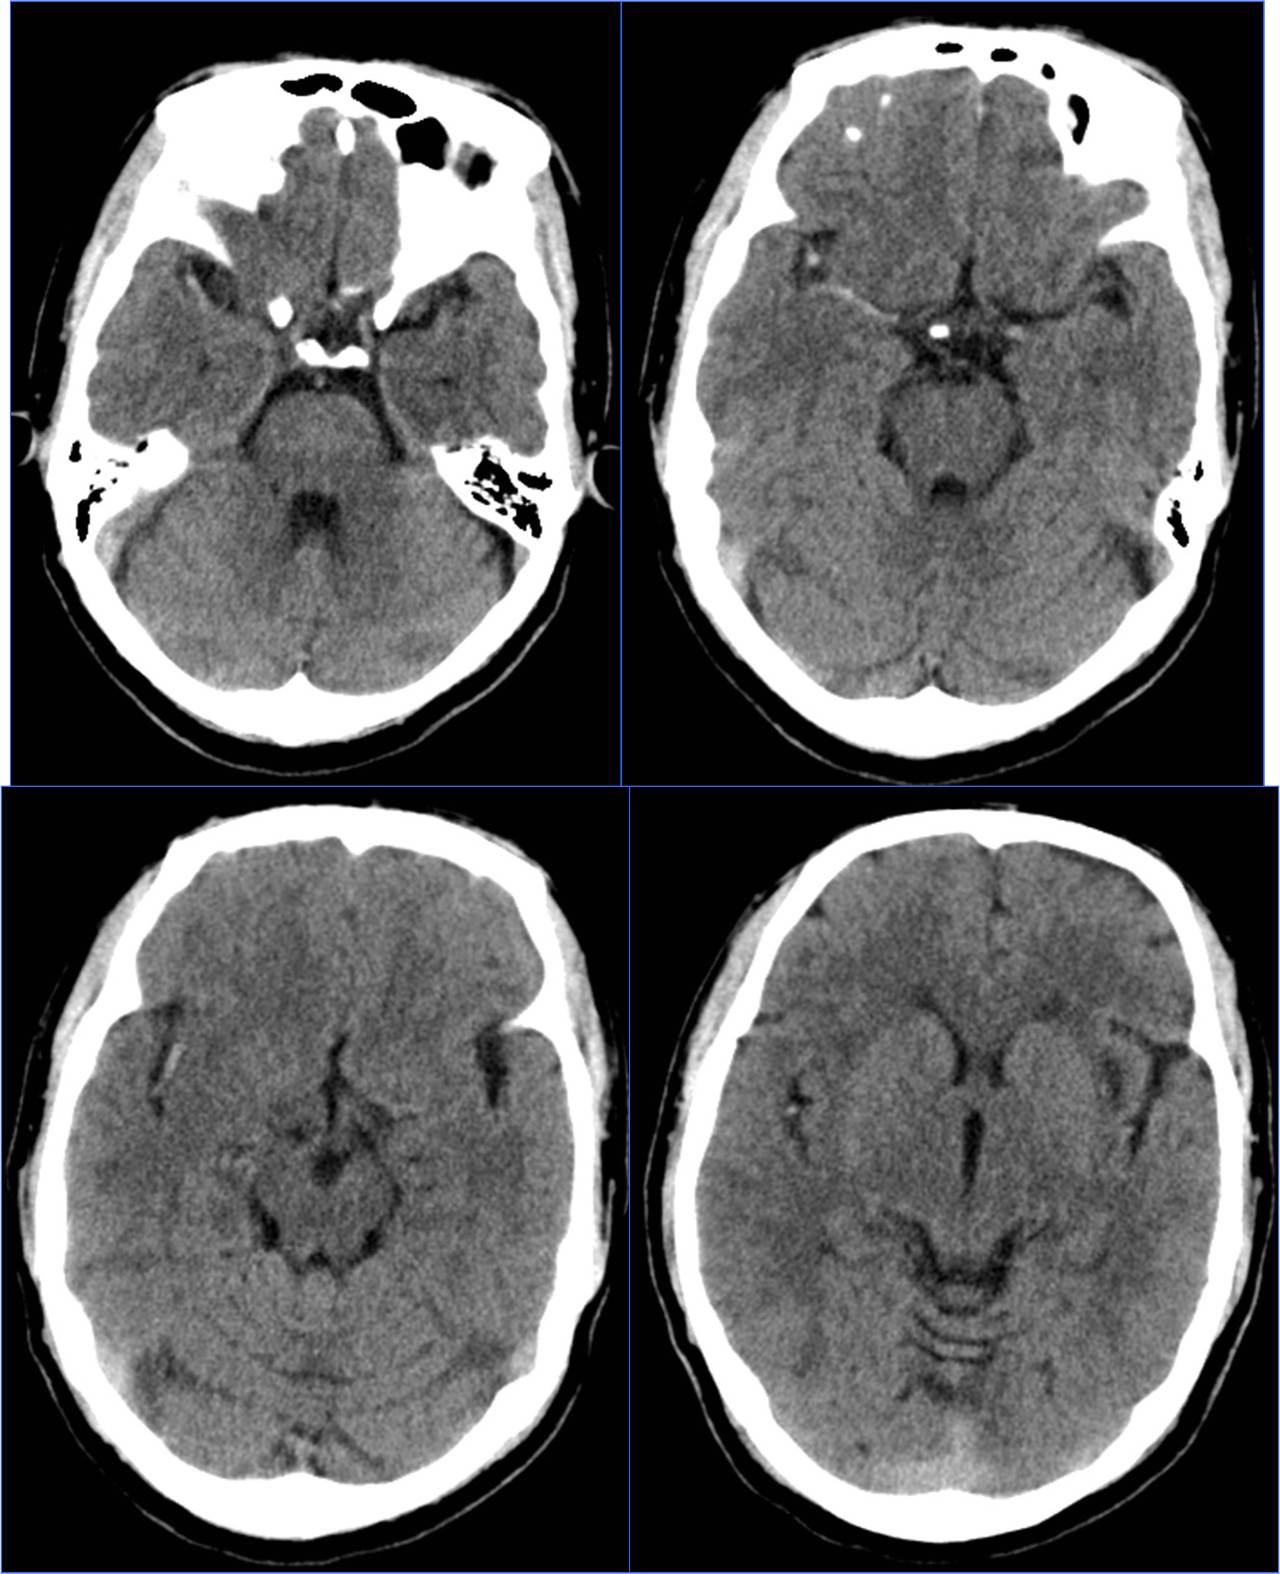

Case1 全麻插管时机选择

》男,60岁。有房颤史。

》7:50三次TIA(发作性右侧肢体无力),8:45到我院急诊,8:52完成头CT检查。

》9:30再次加重,11:30通知介入医师。

》NIHSS评分10分。

》12:20股动脉穿刺。

》12:50血管再通。

》10天后出院,NIHSS 0分。

》全身麻醉。

▼左侧大脑中动脉高密度征

▼气管插管时机:释放支架重建血流后

术前静脉溶栓

术中动脉溶栓

心源性栓塞出血转化